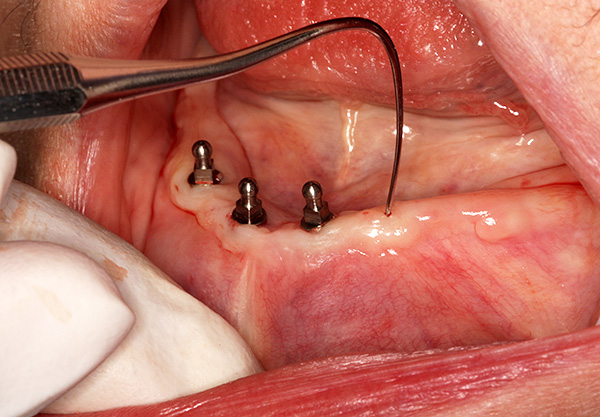

No caso comum, a prótese é instalada alguns dias após o implante. As impressões são feitas imediatamente após a fixação dos implantes e a técnica é dada ao laboratório.

Às vezes, de acordo com o médico, é possível causar uma impressão antes da instalação dos implantes, para que a prótese esteja pronta para o procedimento e o médico a instale imediatamente após o implante. No entanto, nesse caso, a posição dos implantes deverá ser “customizada” para encaixar os ninhos na prótese e, em casos raros, são possíveis inconsistências.

Da mesma forma, é possível instalar uma prótese já nos mini-implantes do paciente se a prótese estiver em boas condições e feita há menos de 2-3 anos. Um sistema de fixação é incorporado a ele antes da operação e é instalado diretamente nos pilares. Depois disso, o paciente pode remover e colocar a prótese para realizar procedimentos de higiene.

Para modificar a prótese antiga, são feitos nele os aprofundamentos dos pilares dos implantes já instalados, estritamente de acordo com sua projeção em uma base plástica, então são instalados acessórios de silicone nesses recessos, e os pilares são inseridos neles, fixando rigidamente a prótese.